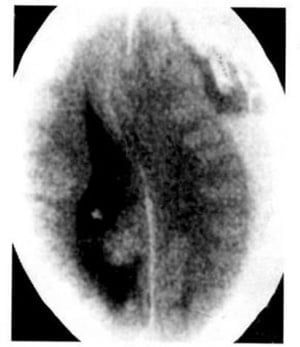

1.9. Lymphoma (Hình 1.35)

Dấu hiệu XQCTĐT:

– Khối u mật độ ngang hoặc cao, giới hạn không rõ, thường nằm sâu trong chất trắng hoặc ở thể trai.

– Hiếm khi đóng vôi

– Ở bệnh nhân AIDS, có thể hoại tử và giống như nhiễm trùng (như nhiễm Toxoplasma) với bắt chất cản quang dạng viền, 50% nhiều tổn thương

Hình 1.35. Lymphoma não. Khối bắt chất cản quang mạnh nằm trong vùng thể trai (a). Những tổn thương dạng đám, rải rác trong chất xám và chất trắng vùng vỏ (b).